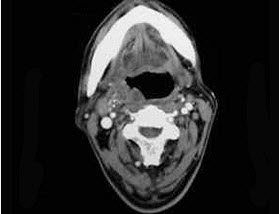

如图,出现咽旁脓肿侵犯颈静脉可出现()。

[单选题,B1型题] 如图,出现咽旁脓肿侵蚀颈动脉可引起()。A . Horner综合征B . 严重出血C . 张口困难D . 喉痉挛E . 血栓性静脉炎

[配伍题,B型题] 出现咽旁脓肿侵蚀颈动脉可引起()一旦咽旁脓肿感染累及翼内肌可引起()如咽旁脓肿侵犯颈交感干可出现()出现咽旁脓肿侵犯颈静脉可出现()A .Horner综合征B .严重出血C .张口困难D .喉痉挛E .血栓性静脉炎

[单选题]出现咽旁脓肿侵蚀颈动脉可引起( )。A.Horner综合征B.严重出血C.张口困难D.喉痉挛E.血栓性静脉炎